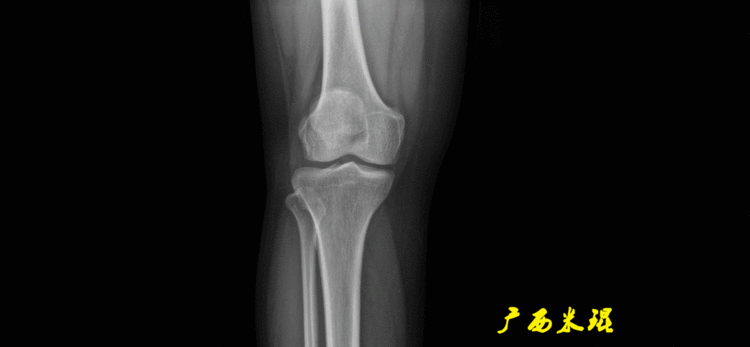

(2)膝关节中心膝关节中心点常用的有5个不同的定位方法,分别是股骨髁中点、股骨髁间窝顶点、膝关节间隙水平软组织中点、胫骨髁间嵴中点和胫骨平台中点,我们可以根据具体情况来选用。

(2)股骨远端关节线正位为股骨内外侧髁最低点之间的连线。髌骨下极在此线之上,距离大于20mm可考虑为高位髌骨。

(3)胫骨近端关节线正位为胫骨内外侧平台最低点之间的连线。

说明一下,膝关节线常常为膝关节间隙的水平线,也是膝关节的轴线,只有在比较正常的关节情况下使用,大多数情况下画出股骨远端机胫骨近端的关节线更好。(4)踝关节线踝关节线为胫骨远端软骨下骨之间的连线。

股骨远端外侧角(mLDFA):股骨内外侧髁远端切线(关节线)与股骨头和膝关节中心的连线(机械轴)两者之间形成的外侧夹角,正常为87°±3°。

胫骨近端内侧角(mMPTA):胫骨内外侧平台切线(关节线)与股骨头和膝关节中心的连线(机械轴)两者之间形成的内侧夹角,正常为87°±3°。

5、画出与解剖轴相关的角度解剖股胫角(aFTA):股骨干下段轴线(解剖轴)与胫骨上段轴线(解剖轴)在膝关节所形成的夹角,正常为174°±1°。膝关节OA的畸形常常由于一侧软组织及关节的过度磨损所致,临床多为内侧磨损过度,因此表现为轻度膝内翻畸形,X线表现为解剖股胫角小于174°,而胫骨角正常。

6、其他角度胫骨股骨关节线夹角(JLCA):胫骨近端关节线与股骨远端关节线之间的夹角,正常生理状态下几乎为0°。当JLCA>2°时提示异常,通常为韧带松弛或者软度磨损丢失所致。